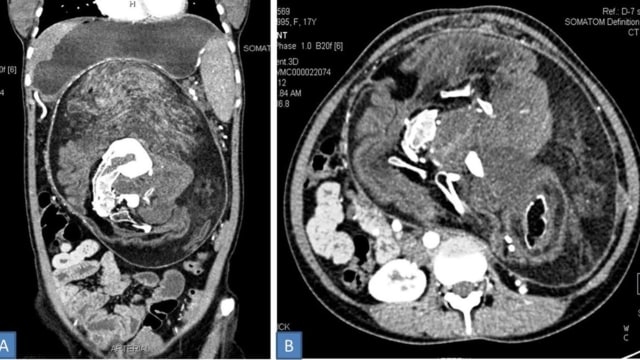

Tapi, pemeriksaan CAT scan menunjukkan adanya deposit kalsium di benjolan yang memiliki bentuk tulang belakang, rusuk, dan tulang panjang. Dokter lalu memutuskan untuk mengangkat "tumor" itu.

Menurut laporan, tumor itu memiliki rambut, tulang dewasa, dan bagian tubuh lainnya, seperti gigi serta struktur yang mirip anggota badan. Ukurannya terbilang besar, yaitu 36×16×10 sentimeter.